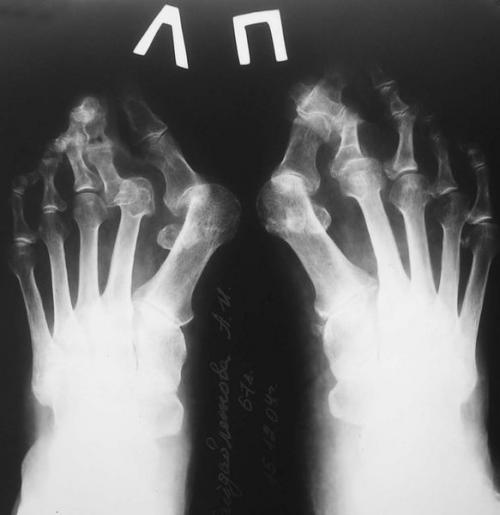

3. Рентгенография. Обследование, выполненное в положении стоя и в двух проекциях, позволяет детализировать степень деформации и выбрать дальнейшую тактику лечения. Основное значение при анализе данных рентгенограмм играют следующие показатели:

- угол наклона дистальной суставной поверхности к оси первой плюсневой кости;

- угол, образованный осями первой и второй плюсневых костей;

- угол отклонения первого пальца от оси первой плюсневой кости;

- угол между осями ногтевой и основной фалангами первого пальца.

Деформирующий артроз плюсне-фаланговых суставов, рентгенография